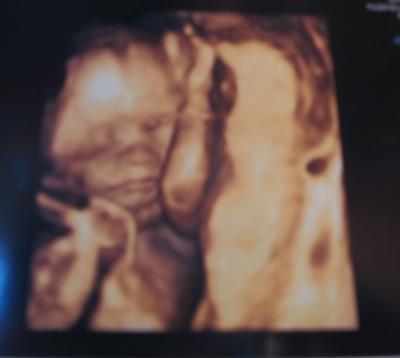

Huhu Mädels!!! Auch ich war heute zur Feindiagnostik!!! Alles ist super mit dem Baby...auf die Fragen, ob wir das Geschlecht wissen wollen, waren meinn und ich uns einig! NEIN...freu...somit werden wir nen Ü-Ei bekommen!!! Ich freu mich schon auf die Geburt!!! Zur Entwicklung sagte der Arzt, dass das Baby schon fast 1,5 Wochen weiter wäre...mal sehen wann das Baby dann kommt!!! Ein wunderschönes 3D-Bild haben wir auch bekommen, nachdem wir schin fast aufgegeben hatten, da das Baby sich immer quer legt und der US schwer war...trotz extremen ruckeln..... Lg Naddel Als hier unser Schatz bei rechnerischem 22+1

Bild zu Organ-US - Forum für September - Mamis